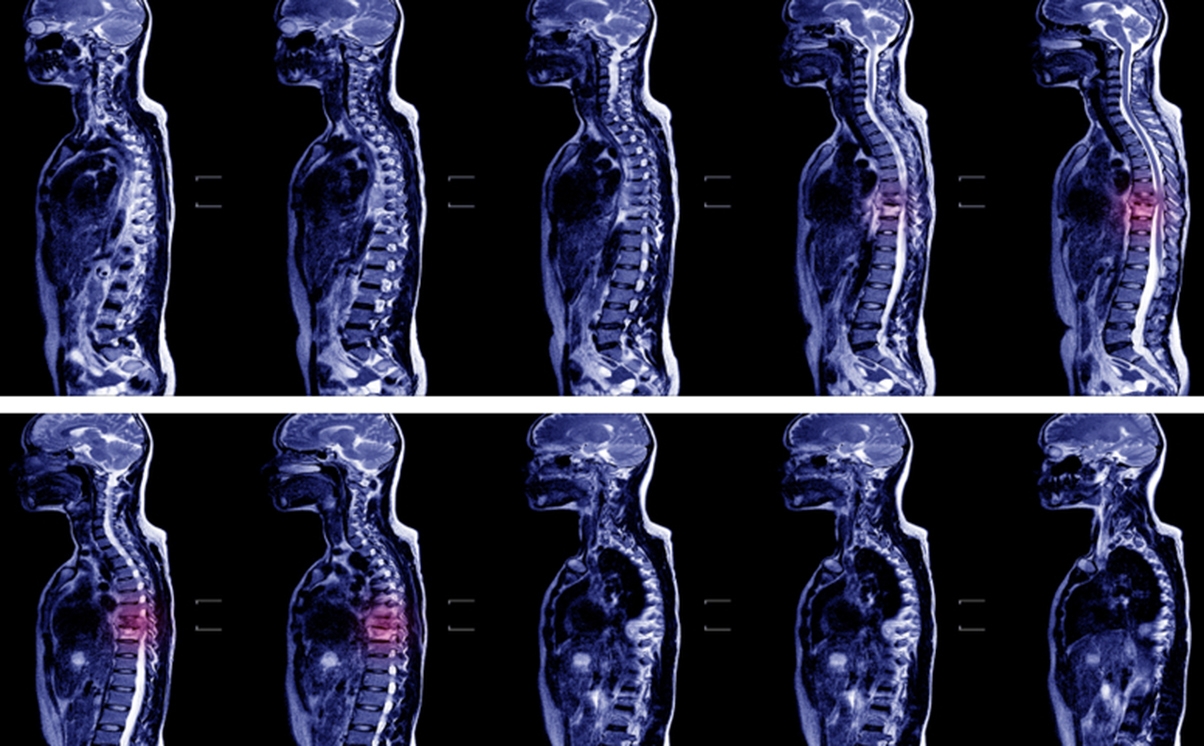

LJ had an MRI scan a week later and was advised that this showed a haematoma, probably caused by the administration of the spinal block, but this would heal.

In November 2013, LJ received a letter from her anaesthetist suggesting that the MRI scan from August in fact showed damage to the lower end of her spinal cord and the spinal block was the likely cause. She met the anaesthetist who was apologetic but did not suggest that the damage was permanent.